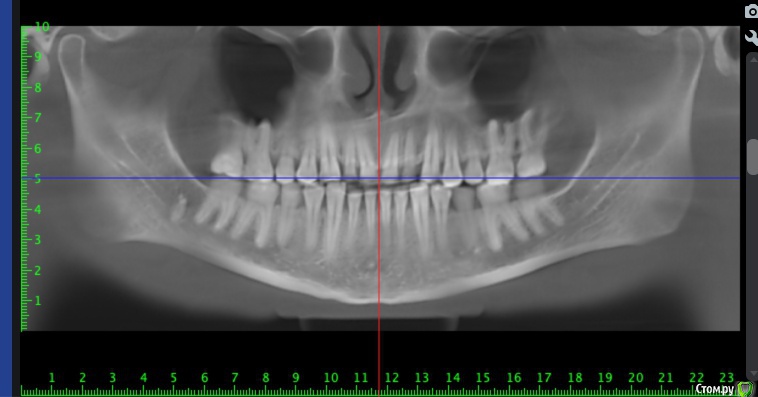

Мне 30 лет, лет 5 назад стоматолог-терапевт заметил излишнюю стираемость, была долгая эпопея с ортодонтическим лечением и вот наконец в прошлом месяце сняли брекеты и теперь настало время ортопедического.

Врач, который работает в паре с ортодонтом настаивает на полном протезировании (спереди виниры emax, сзади накладки так же из керамики). Со слов врача после диагностики сустава стало понятно, что чем выше поднимем прикус тем лучше, так должен уйти бруксизм, который сейчас присутствует.

Альтернативное мнение, которые я получил, что можно сделать накладки только на 5/6/7 со всех сторон, восстановить клыки композитом для "клыкового ведения" и пока все - полное протезирование всегда успеется. Может быть немного пожертвовав высотой прикуса.

По мнению первого врача, если делать только жевательные зубы выводя на нужную высоту прикуса, то передние зубы не сомкнутся и это нехорошо.

п.с. На некоторых зубых есть временные накладки, которые делали на время отродонтического лечения.